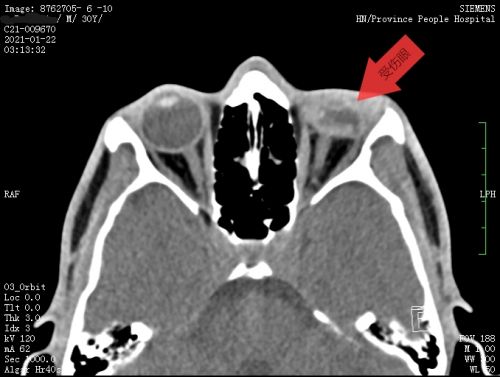

患者眼眶ct显示,左眼球塌陷、变小,眼内结构紊乱。